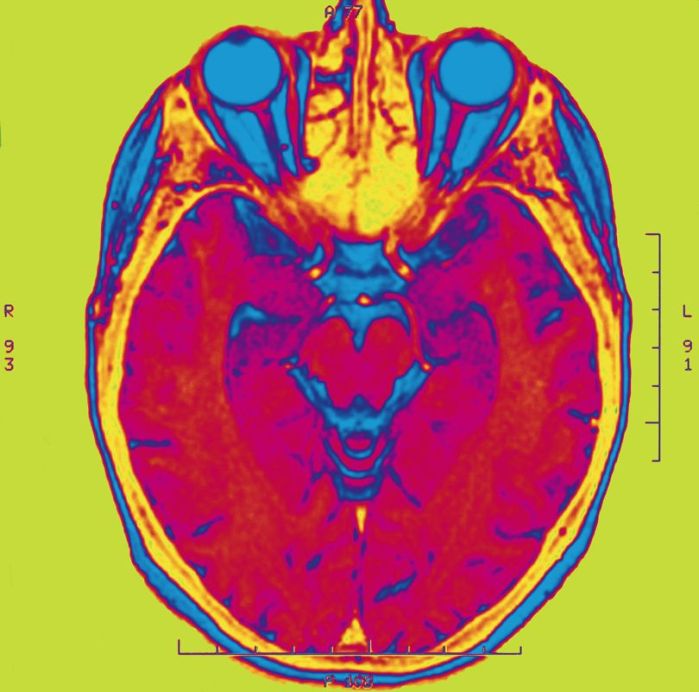

Theo một nghiên cứu mới, chụp Cộng hưởng từ (MRI: Magnetic Resonance Imaging) có thể hỗ trợ việc phát hiện những dấu hiệu ban đầu về vấn đề sức khỏe tâm thần ở thanh thiếu niên.

Được xuất bản trong Tập san Kỷ yếu của Viện hàn lâm Khoa học (Proceedings of the National Academy of Sciences), nghiên cứu này bao gồm việc sử dụng Cộng hưởng từ để theo dõi sự phát triển của não bộ thanh thiếu niên và từ đó lập bản đồ các kết quả MRI đối với cơ sở dữ liệu Allen Brain Atlas[1] về biểu hiện gen.

Các nhà nghiên cứu phát hiện ra rằng những khu vực có những thay đổi lớn nhất (đo lường bằng MRI) là những khu vực có liên quan đến nguy cơ của chứng tâm thần phân liệt. Điểm mấu chốt của phát hiện này dựa trên những kiến thức thực hành trước đó, rằng myelin – một vỏ bọc bảo vệ các sợi thần kinh và hỗ trợ giao tiếp – có thể được tìm thấy cả trong ‘chất xám’, chứ không chỉ trong ‘chất trắng’, với mức độ gia tăng rõ rệt trong suốt giai đoạn thanh thiếu niên. Đồng thời, các khu vực bên ngoài của vỏ não teo lại theo thời gian.